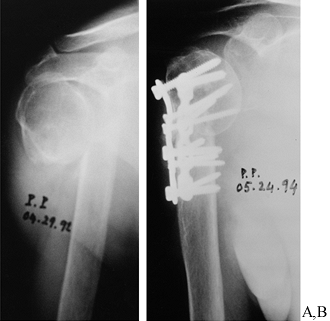

Figure 27.7. Hemiarthroplasty for a malunited fracture of the proximal humerus. A:

Malunion of a displaced four-part proximal humeral fracture. The glenoid is empty, and the humeral head fragment is rotated 180° laterally. This patient had significant pain and limited shoulder function. B: A CT scan of the shoulder shows the malunited humeral head in its rotated position. The greater tuberosity can be seen laterally to the head and appears to be not united in this picture. Notice the sclerotic humeral head, indicating avascular necrosis. C, D: A Neer hemiarthroplasty was inserted for the primary relief of pain. At the time of surgery, the humeral head was osteotomized and excised, and 90° of forward motion was obtainable in the operating room under anesthesia. The patient has done relatively well after surgery; he has mild residual pain with adequate function. |